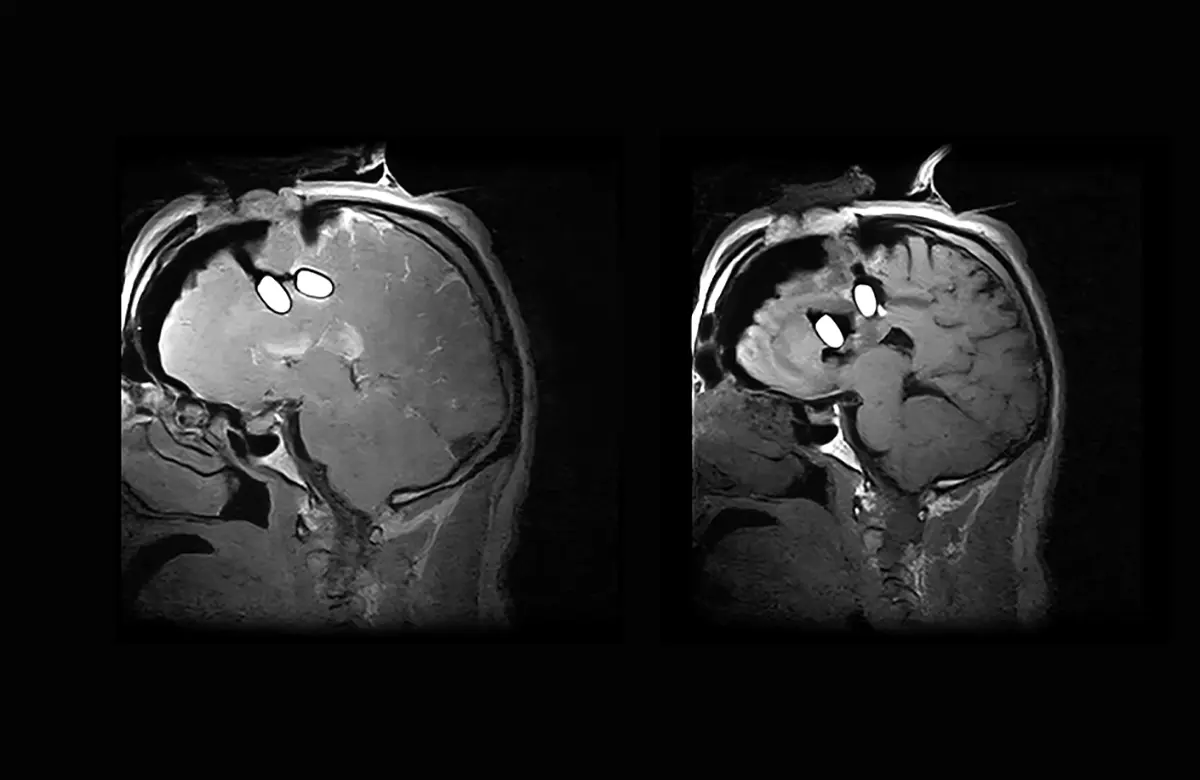

Intraoperative MRI with I‑Genius transforms the practice of brain tumor surgery by allowing MR imaging directly in the operating room, eliminating patient transfer and giving surgeons greater confidence in achieving a more complete and safer resection.

Advanced intraoperative imaging provides neurosurgeons with the clarity, and confidence required to make important decisions in critical moments.

What is truly innovative about I‑Genius is its ability to provide intraoperative imaging at every stage of neurosurgery. This allows the surgeon to resect the lesion, immediately verify the result, reassess how to proceed with precision and safety, and then confidently continue the procedure.

This process can be repeated as many times as the surgeon deems necessary during the operation, culminating in a final check that provides the certainty of having achieved the maximum safe resection of the tumor while preserving the healthy brain and the patient’s neurological functions”.